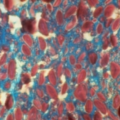

Des produits dérivés de plantes présentent un potentiel thérapeutique contre le neuropaludisme

Vie et Terre